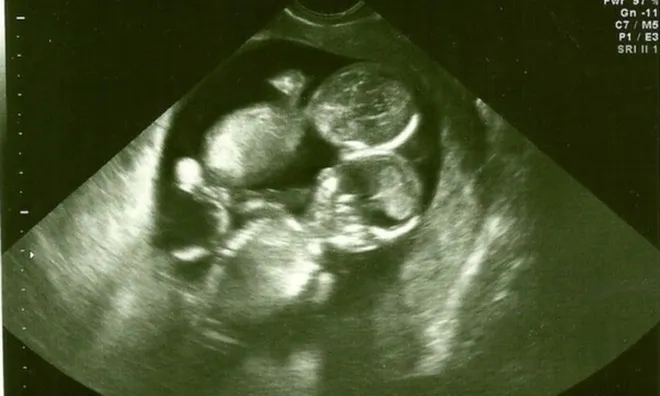

Cặp sinh đôi mắc bệnh hiếm, hai dây rốn đan nhau như tết tóc vẫn sống sót kỳ diệu, chào đời cực xinh

Người mẹ cãi lời bác sĩ và cái kết khó tin.